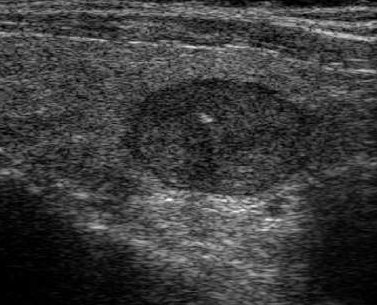

Nodular Diseases In The Thyroid - Journal Of Association Of ...

Lymphoma as well as metastasis to the thyroid gland. The important causes are listed in table 1. follicular neoplasm and Hurthle neoplasms, from malignant thyroid lesions.16 It has been shown that over ... Retrieve Here